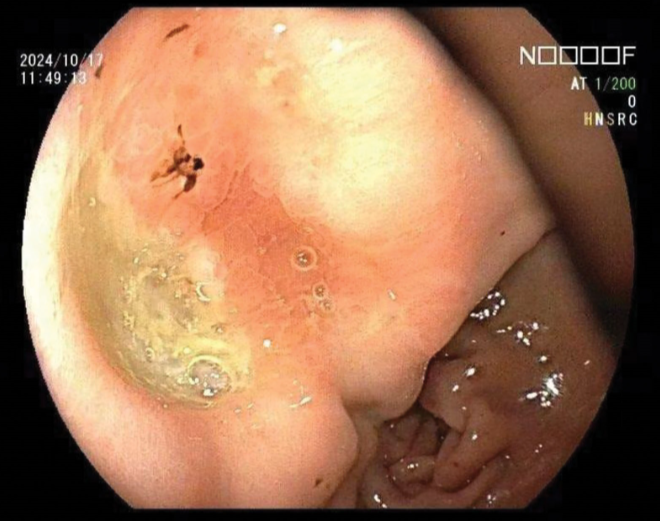

胃镜检查显示,胃窦小弯处可见一大小约1.2 cm的不规则凹陷性溃疡,底部覆有黄白苔和污秽苔,周围黏膜水肿,活检组织质韧且易出血(图1)。

图1. 胃窦小弯侧观察到一处不规则凹陷性溃疡,溃疡底部覆盖黄白色污秽物,周围黏膜水肿,质地坚韧,易出血。